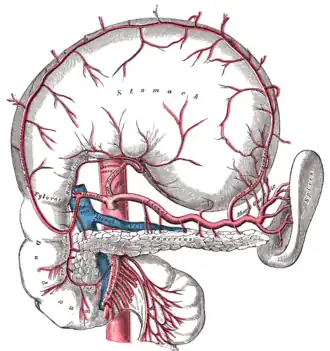

La vascularisation artérielle de la rate se fait principalement par l'artère splénique (artère liénale). Celle-ci étant l'une des 3 branches du tronc cœliaque qui naît de l'aorte au niveau de la 12e vertèbre thoracique. Après un trajet très sinueux sur le bord supérieur du pancréas, elle pénètre dans le parenchyme par le hile en se divisant en deux branches supérieure et inférieure ; ceci explique l'existence de la splénectomie partielle. Ensuite ces branches se divisent en artères trabéculaires qui cheminent dans les travées conjonctives. Elles-mêmes donnent les artères centrales en sortant de la travée, qui s'entourent d'un manchon de pulpe blanche (surtout lymphocytes T). L'artère centrale se poursuit et sort de la pulpe blanche pour donner des plus petites branches : les « artères pénicillées ». Celles-ci se finissent par des capillaires avec des sortes de bouchons qui entourent leur terminaison : ce sont les capillaires à housse. Ces capillaires terminaux sont obturés et il va y avoir des passages entre les cellules endothéliales terminales, et le sang va sortir des vaisseaux et traverser le parenchyme splénique pour rejoindre les sinus veineux. On a donc une circulation fermée et une circulation ouverte.

La vascularisation veineuse se fait quant à elle par la veine splénique (veine liénale), qui rentre dans la constitution du tronc porte avec les veines mésentériques supérieure et inférieure.

Le tronc cœliaque et ses branches.